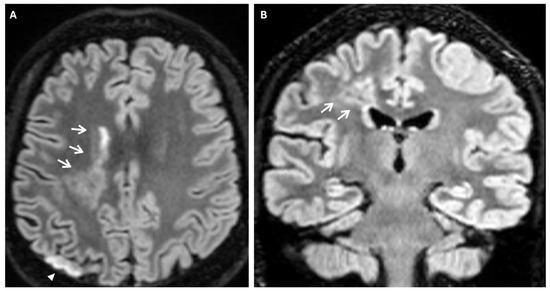

Another phenomenon that can be observed on FLAIR sequences is the “medullary streak” sign, which is characterized by a hyperintense streak oriented perpendicularly to the lateral ventricle (“periventricular medullary veins/FLAIR hyperintense streaks”); despite its etiology remaining ambiguous, the condition has been associated with ischemia and could represent collateral vasculature, stagnated cerebrospinal fluid, or vasogenic edema (Figure 7).

Figure 7. Axial (A) and coronal (B) 3d FLAIR sequences show a hyperintense streak area oriented perpendicularly to the right lateral ventricle (white arrows), representing the “medullary streak” sign. Note the right parietal subacute ischemic lesion (white arrowhead).